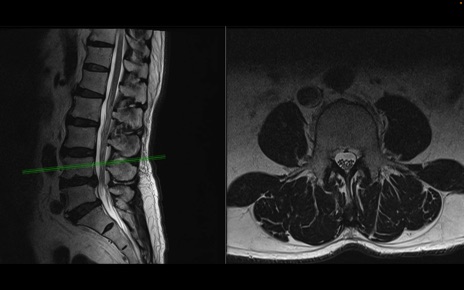

【整形】TIPS症例2 腰椎MRI 横断像と矢状断像

【症例】70歳代男性

【主訴】左下肢痛

【現病歴】2週間前くらいから腰痛、左下肢痛あり。左臀部から大腿、下腿外側のしびれが常時ある。歩行とともに同部位の痛みあり。

【身体所見】Lasegue70-/60+、Bragard-/±、PTR ±/±、ATR -/-、IP 5/5、TA 5/4、TS 5/5、EHL 右第1足趾なし/3、FHL 5/5、hypersthesia(-)、足背動脈触知良好

異常所見と診断は?